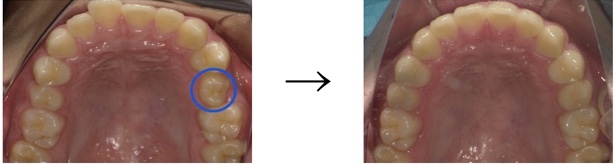

◼︎上顎 Before→After

ねじれていた歯の向きを正しい向きに整え、やすりがけを行い、飛び出ていた歯がきちんと歯列におさまりました。